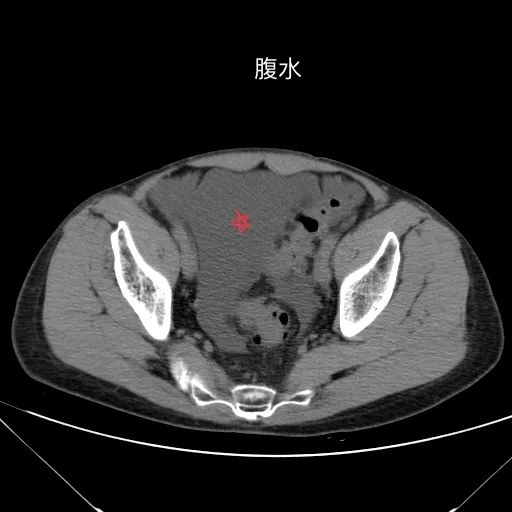

肝脏缩小,包膜凹凸不平,肝裂增宽,各叶比例失衡,肝实质密度不均,肝S4小片低密度影,约cm;胆囊不大,其内未见异常密度影,胆道系统未见扩张;胰腺、脾脏形态、密度、大小未见异常;双肾上腺及双肾形态、密度、大小未见异常,双输尿管未见扩张,膀胱充盈良好,壁光滑,其内未见异常密度影;前列腺未见异常;胃肠道未见充盈,壁未见明确增厚,食管胃底多发迂曲、增粗血管,腹部及腹膜后未见肿大淋巴结;腹水。

1.肝硬化失代偿表现(腹水,食管胃底静脉曲张)。